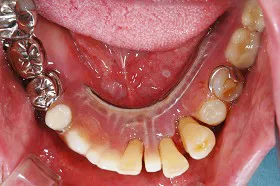

インプラント治療及び補綴治療のケース

■治療前:奥歯が無いため噛み合わせが深く下の歯が全く見えない

噛み合わせが低いため全体的に歯が削れている

■治療後:下顎 左下5・6番、右下4・6番にインプラント治療

その他の歯に補綴治療をしたことにより、奥歯もしっかりと咬むことができ、奥歯ができたことにより噛み合わせも上がって下の歯も見えるようになり、審美的にも改善された

| 主訴 | 歯科治療をしても歯がすぐに欠けてしまう 奥歯が無いため、奥歯で咬めない |

| 治療方法 | インプラント治療 + 補綴治療 |

| 治療期間 | 約1年 |

| 通院回数等 | 約20回 |

| 費用 | 約250万円(税込) |

| リスク・副作用 | 術後の腫れ・痛み |